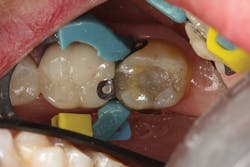

The difference in using this product over standard- or non-bulk-fill composites comes in the filling technique. The manufacturer states that you can predictably cure an increment of this composite up to 4 mm in depth. This assumes the light energy coming from your curing light is ideally positioned and is functioning properly (power intensity of 1000 mW/cm2 or greater). For carious lesions that are relatively small to moderate in size (figures 1a and 1b), this translates, in general, to being able to place one increment of composite that fills partway up the proximal box to the level of the contact and onto the occlusal pulpal floor (figure 2). The second increment could then be placed on top, which would fill the rest of the restoration.

However, as mentioned earlier, getting the composite adapted to both the buccal and lingual cavosurfaces at the same time can be tricky. To address this, I have found it easier to place one increment of resin in a way that covers the entire buccal side of the preparation, including the marginal ridge area (figure 2), and light cure it prior to finishing the fill with the lingual increment. This requires one extra step, but it gives me the peace of mind that I am reducing the polymerization shrinkage on the opposing cavosurfaces as well as eliminating the back and forth nature of trying to adapt the composite to both sides of the cavity preparation (figure 3).